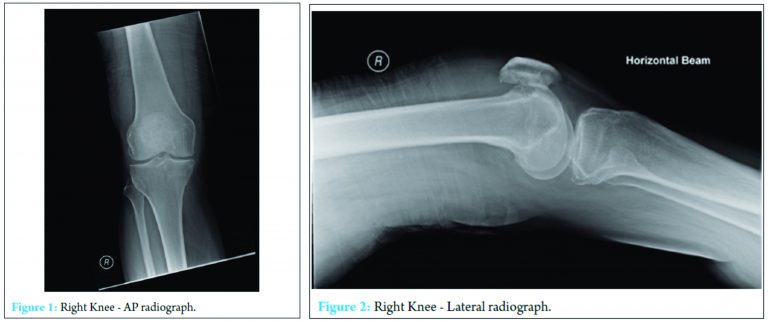

A 69-year-old patient presented to the emergency department (ED) with a 3-day history of a red, hot, and swollen right knee. The patient had fallen onto his right knee 3 days before current presentation. Medical history included gout of his right first metatarsal. The patient was otherwise well, had never smoked and drank minimal alcohol. He lived with his wife and was self-caring. On examination, the patient was afebrile but flushed, slightly confused, and disorientated. The knee was objectively swollen and hot compared to the contralateral limb. There was a positive patella tap with joint tenderness. He was unable to actively straight leg raise (SLR) or flex his knee. Pain-free passive movements were obtained, SLR limited to 45° and knee flexion to 30°. The limb was neurovascularly intact. Examination of the right hip and ankle were found to be normal. AP and lateral radiographs of the right knee (Fig. 1 and 2) demonstrated chondrocalcinosis and an effusion with a background of osteoarthritic changes in both medial and lateral joint spaces. There was no fracture. Radiographs of both the hip and ankle were normal. A head computerized tomography was performed due to the confusion and a history of a fall, which was found to be normal. Bloods test revealed acute derangements of biochemistry and inflammatory markers: Creatine kinase – 3936, urea – 25.3, creatinine – 260, eGFR – 21, sodium – 130 and potassium – 3.8, CRP: 520, WCC 8.5. Sinus tachycardia and right bundle branch block were demonstrated on a 12-lead ECG. Preliminary results of the knee aspirate identified 2+WBC and no organism or crystals. The patient was admitted under joint orthopedic and medical care and based on chondrocalcinosis being present on the radiograph, was treated for crystal synovitis in addition to rhabdomylosis, acute renal failure and dehydration with intravenous fluid hydration, antibiotics and analgesia. On the post take ward round, the patient was found to be febrile and septic. Microbiology results of the right knee aspirate grew Group B Streptococcus, and the patient was taken to theater for arthroscopic washout. Intraoperatively this demonstrated pus. IV antibiotics were changed according to local policy to flucloxacillin and benzylpenicillin.